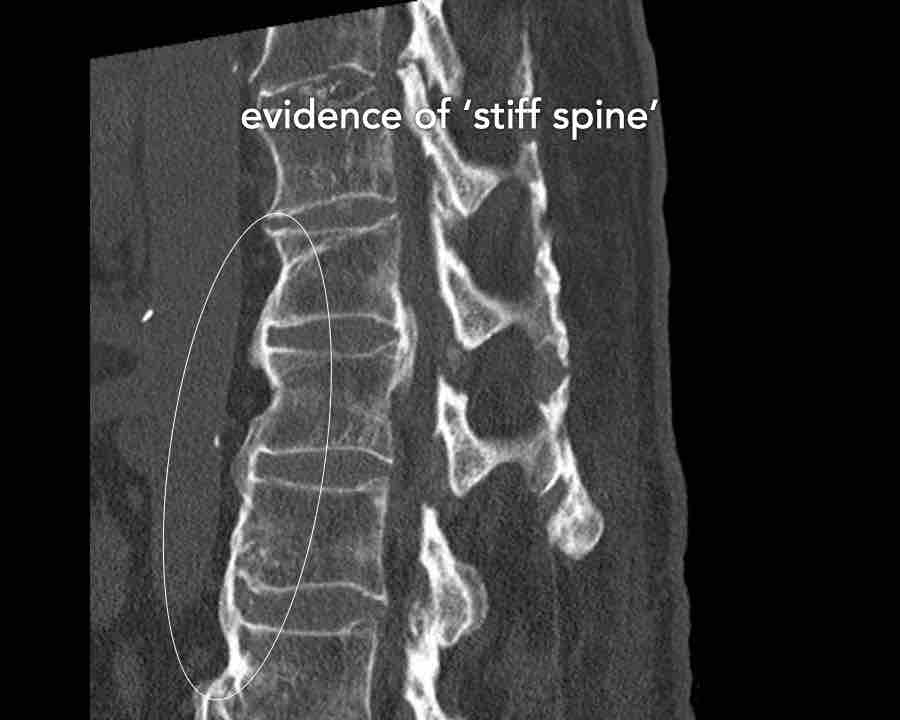

These injuries can be difficult to detect since patients are scanned in the supine position laying on their back, which may obscure the anterior distraction.

However, these injuries mainly occur in patients with a rigid spine as a result of osteoarthritis, DISH or Ankylosing Spondylitis (SpA).

Stay persistent when examining a patient with a rigid spine until you have found the B3 injury.

Scroll through images.

What are the findings?

Findings

- C injury? No.

- Signs of a rigid spine?

Yes, clear example of SpA so be aware of a B3 injury. - Horizontal fracture of vertebral body (white circle)

- Subtle separation anteriorly at the fracture level

Conclusion

injury type B3.